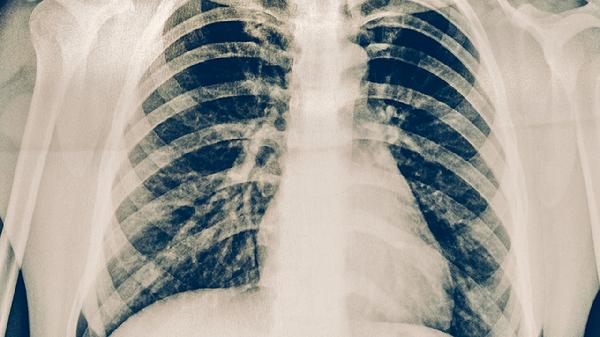

肺結核與肺癌并存的治療

肺結核與肺癌并存時需采取綜合治療策略,主要包含抗結核治療、腫瘤針對性治療及支持治療。兩種疾病并存可能增加治療難度,需由呼吸科、腫瘤科等多學科團隊協(xié)作制定個體化方案。

兩種疾病并存易導致肺部感染、呼吸衰竭等并發(fā)癥。需定期進行痰培養(yǎng)、胸部CT評估,出現(xiàn)發(fā)熱、咯血等癥狀時及時排查感染加重或腫瘤進展。結核病灶周圍纖維化可能影響放療定位,需通過呼吸門控技術提高精度?;熀罅<毎狈ζ谛桀A防結核復發(fā),必要時給予預防性抗結核治療。合并糖尿病等基礎疾病者需強化血糖控制。